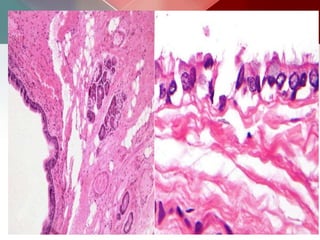

Outer acellular laminated membrane, Germinal membrane& Protoscolices, attached and

budding from the membrane

Microscopically:

 Lined by secretory respiratory epithelium

(cuboid or columnar ciliated epithelium)

 Wall-cartilage, elastic tissues, mucous glands and

smooth muscle

 They do not usually communicate with the

bronchial tree, and are therefore typically not

air filled.

 Contain fluid (water), variable amounts of

proteinaceous material, blood products, and

calcium oxalate